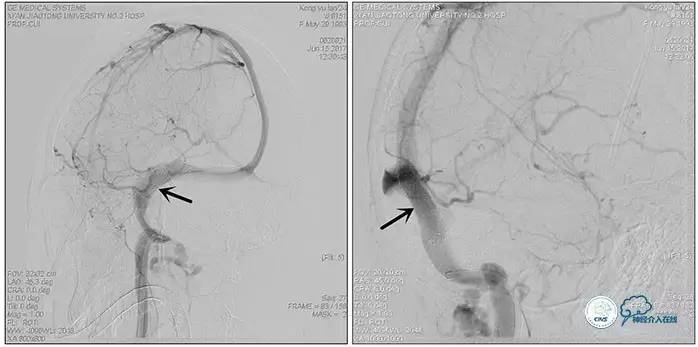

术后右侧ICA造影

术后远、近端压力差为:0

术后右侧ICA斜位

结果

术后即刻患者诉头痛完全缓解。

双眼视力较前有改善。

3天后腰穿:颅内压:75mmH2O,转当地医院眼科继续治疗。